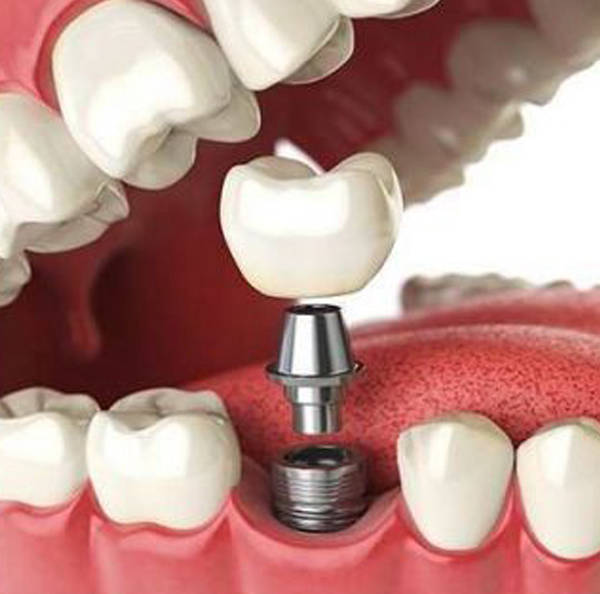

Vem de uma família tradicional de dentistas, iniciou sua carreira em clínicas da família, onde ganhou a prática em lidar com pessoas no seu dia a dia. Amante de cirurgia, fez residência em cirurgia oral menor no Hospital federal do Andaraí, e com o passar dos anos aprimorou seus conhecimentos através de cursos e congressos. Focada na área da estética, a Dra Juliana Audi Lima é especialista em Prótese Dentária e se dedica absolutamente em proporcionar uma melhor qualidade de vida e estética aos seus pacientes. Além de membro da Associação Brasileira de Odontologia, faz parte do seu corpo de professores desde 2017. Atua em Cirurgias, Implantes dentários, Prótese e Ortodontia

*Implante Dentário